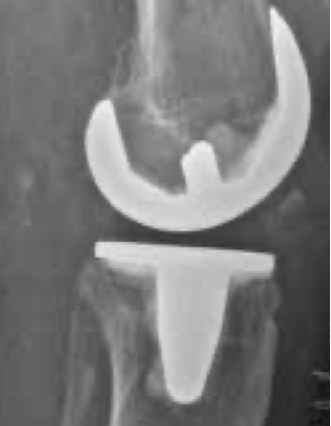

Implantation einer Knietotalendoprothese